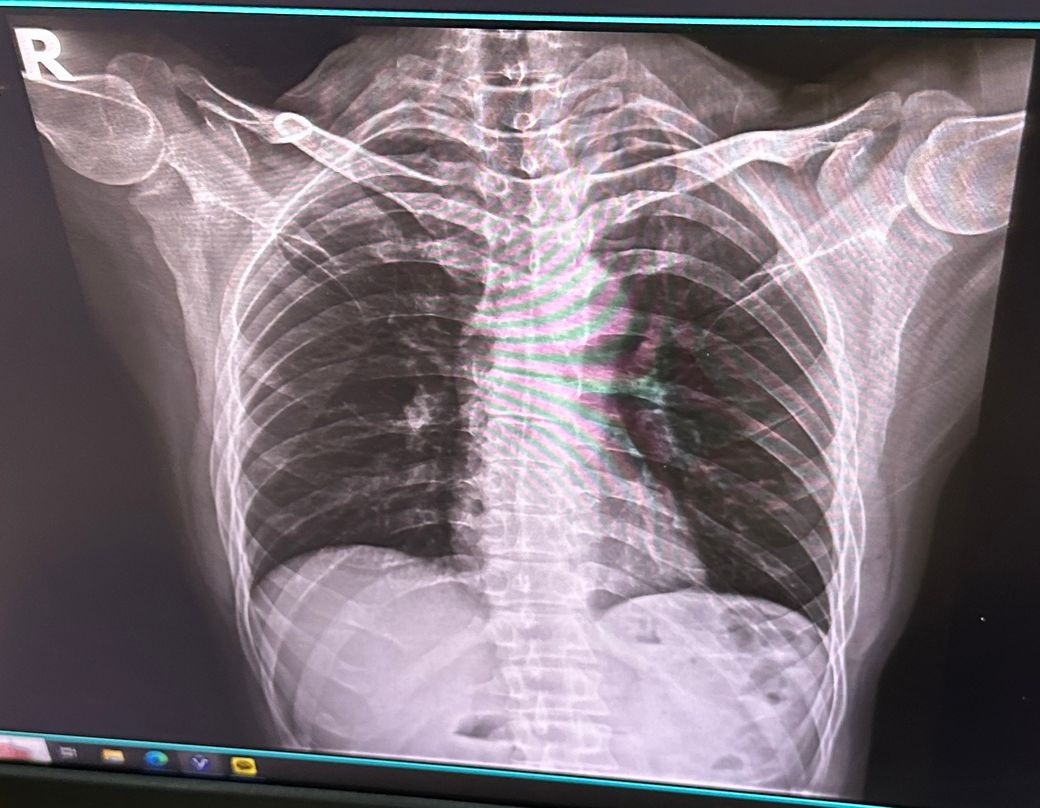

• 3번 째 사진

측만증이 다양한 원인이 있지만 엑스레이 상에서 보아도 측만증이 있어보이긴 합니다. 근데 측만증이라는게 선천적일수도 있고 후천적일 수도 있고 이에따라 치료법이 다르고.. 또한 내가 등이 아프면서 안아프게 하려고 몸을 꼬니까 측만증이 있는것처럼 보일 수 있습니다.

사진상으로 많은걸확인할수는없지만 지금가지고있는 측만증의경우 자세적인문제가있을수있는데요 잠을자거나 휴식을취할때 엎드리거나 만세를하고있는동작은 목어깨나 허리, 몸에 부담을줄수있기때문에 추천하지않습니다

측만증은 일반적으로 유전적 요인이나 오래된 잘못된 자세로 인해 발생할 수 있으며 급격한 통증이 나타나지 않으면 그 자체로 큰 문제가 되지 않는 경우도 많습니다. 신경 부종은 압박에 의해 발생할 수 있으며 잘못된 자세나 장시간 앉는 습관이 영향을 미칠 수 있습니다.